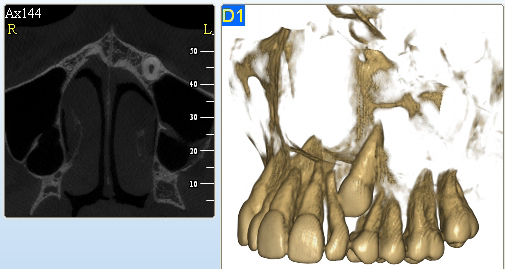

3D DVT - NewTom

Je speciální zubní digitální tříprostorový tomograf (3D), který umožňuje na základě jediného

snímkování vytvořit všechny typy RTG zobrazení, které jsou pro lékaře potřebné. Díky používané technologii tzv. „kuželového paprsku“ a speciálním senzorům je

výrazně zmenšená dávka záření - o více jak 80% proti klasickému CT vyšetření. To je významné zejména u dětí. Pomocí tohoto přístroje je možné zjisti skutečnou situaci v čelistních kostech pacienta tedy množství kosti - můžeme změřit skutečnou šířku i výšku kosti, i kvalitu kosti (hustotu) v místě uvažované implantace. 3D (tříprostorové) zobrazení umožňuje zvýšit prostorovou představu operatéra ještě před vlastní operací a zároveň pacientovi lépe objasnit a ukázat oblast plánovaného zavedení implantátu.

Pacient „neumí číst“ RTG snímky, ale díky 3D zobrazení vidí „svoji skutečnou čelist“

- např. jak je nízká či úzká, vidí průběh nervu nebo velikost čelistní dutiny, což mu umožní i pochopení nutnosti v některých případech provést pomocné zákroky ještě před vlastním zavedením implantátu (viz. kostní štěp, sinus lift, kostní granulát...).

Vyšetření pomocí tohoto přístroje používáme i ve stomatochirurgii (zlomeniny čelistí, zuby moudrosti, cysty, onemocnění čelistního kloubu), ortodoncii (retinované zuby, nadpočetné zuby), parodontologii atd.